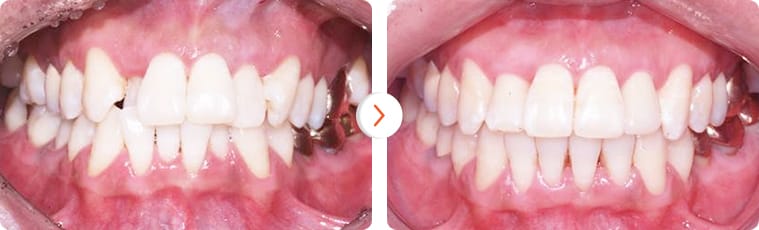

“Khách hàng nam 30 tuổi chỉnh hình răng sử dụng minivis sau 15 tháng”

Trường hợp lệch khớp cắn nhẹ. Bệnh nhân nữ 25 tuổi – Thời gian điều trị: 8 tháng